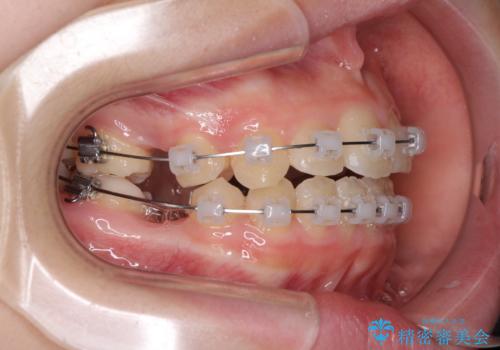

- 矯正装置

- クリアブラケット

- 治療期間

- 2年1ヶ月

- 治療回数

- 10-30回